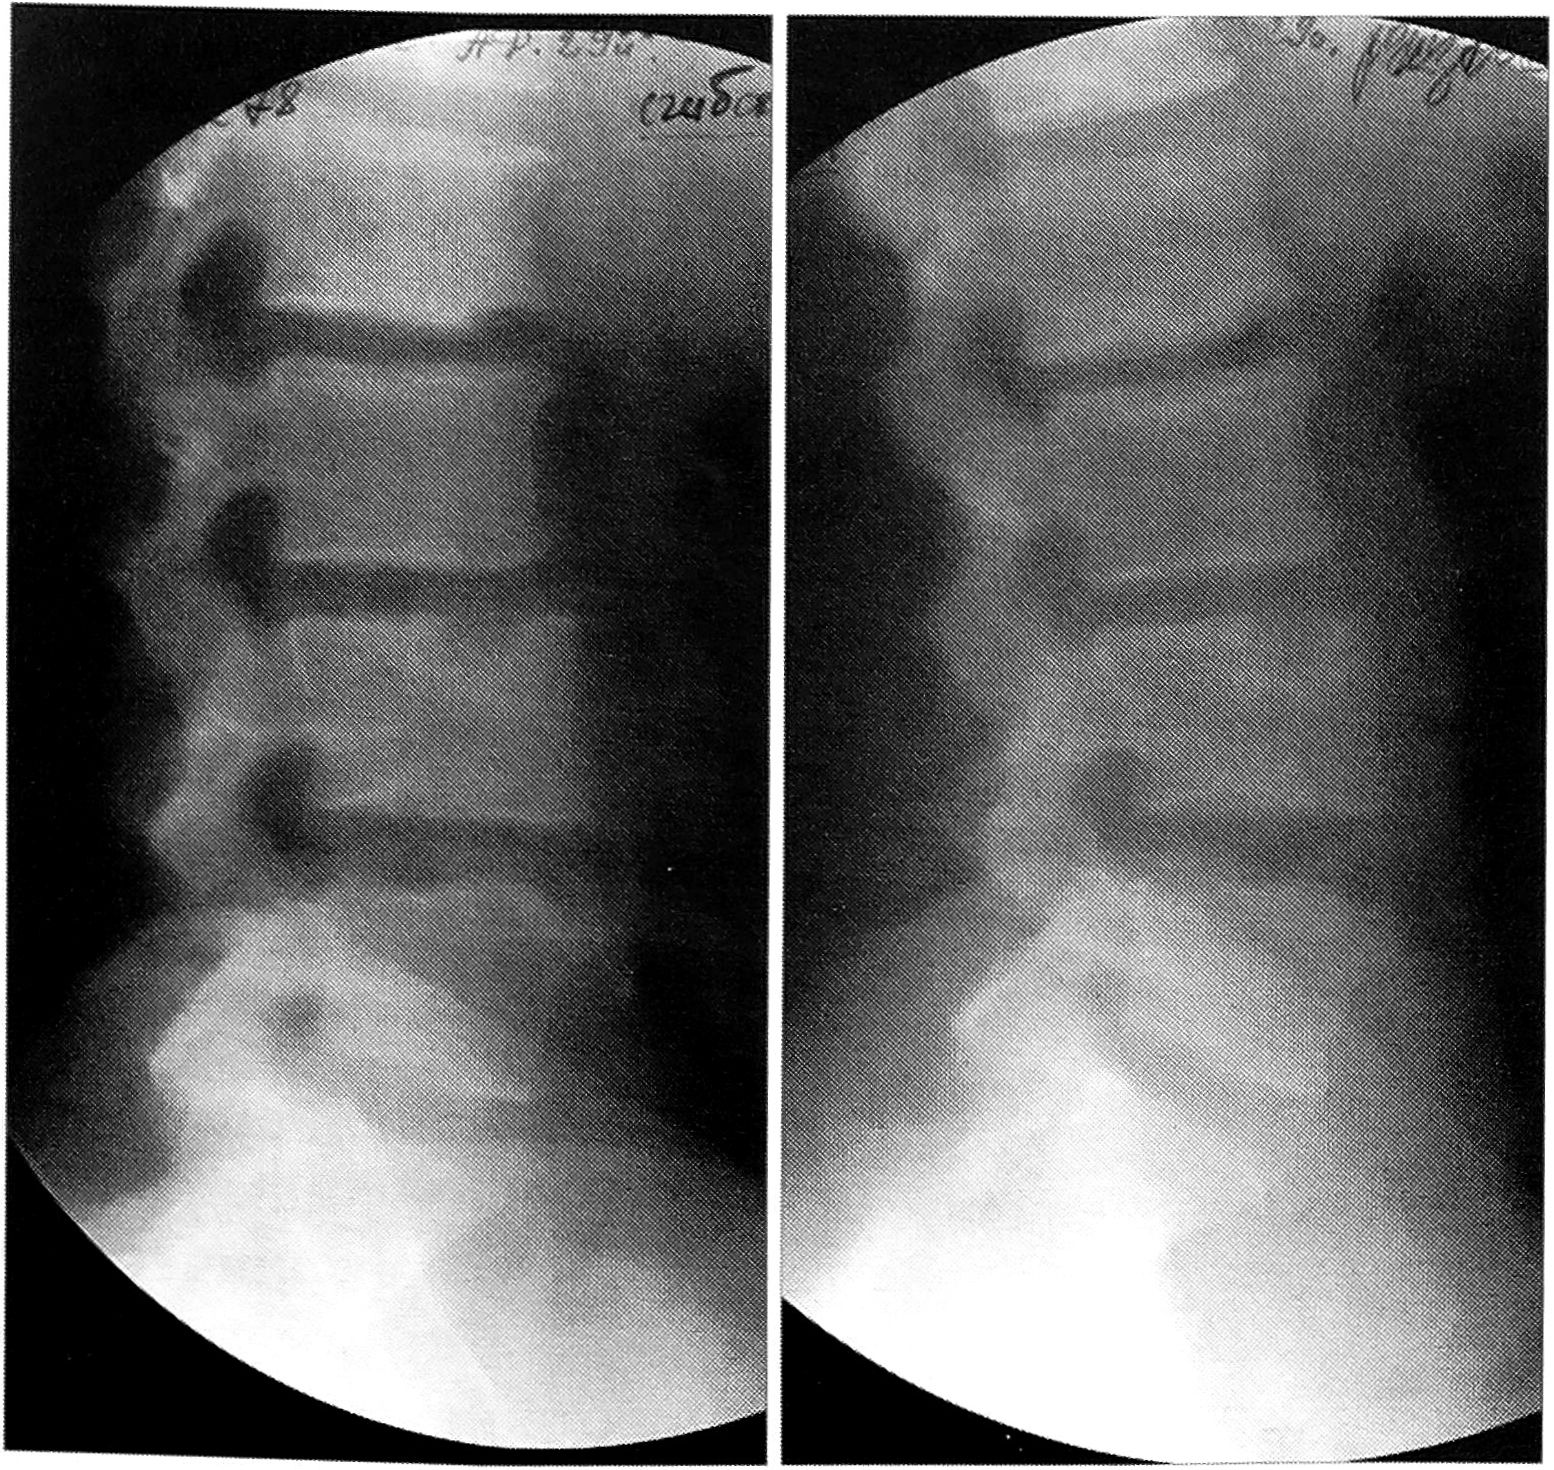

Своеобразным саногенетическим механизмом, снижающим избыточное внутридисковое давление, является интраспонгиозное пролабирование студенистого ядра межпозвонкового диска через ослабленные замыкательные пластинки тел позвонков. Такая потеря вещества диска сопровождается прогрессирующей диффузной дегенерацией элементов диска, его фибротизацией и «естественной» стабилизацией позвоночного сегмента (рис. 5)

Рис. 5. Фиброз L3-4 диска («естественная» стабилизация сегмента с грыжей Шморля L4 позвонка).

Следовательно, в ПДС с грыжей Шморля потеря двигательной функции компенсирует опорную и защитную функции сегмента, и система «возвращается» в состояние потенциального отказа. Формирование внутрикостных грыж Шморля может сопровождаться болевым синдромом по типу химического радикулита вследствие раздражения волокон синувертебрального нерва биологически активными продуктами реактивного воспаления.